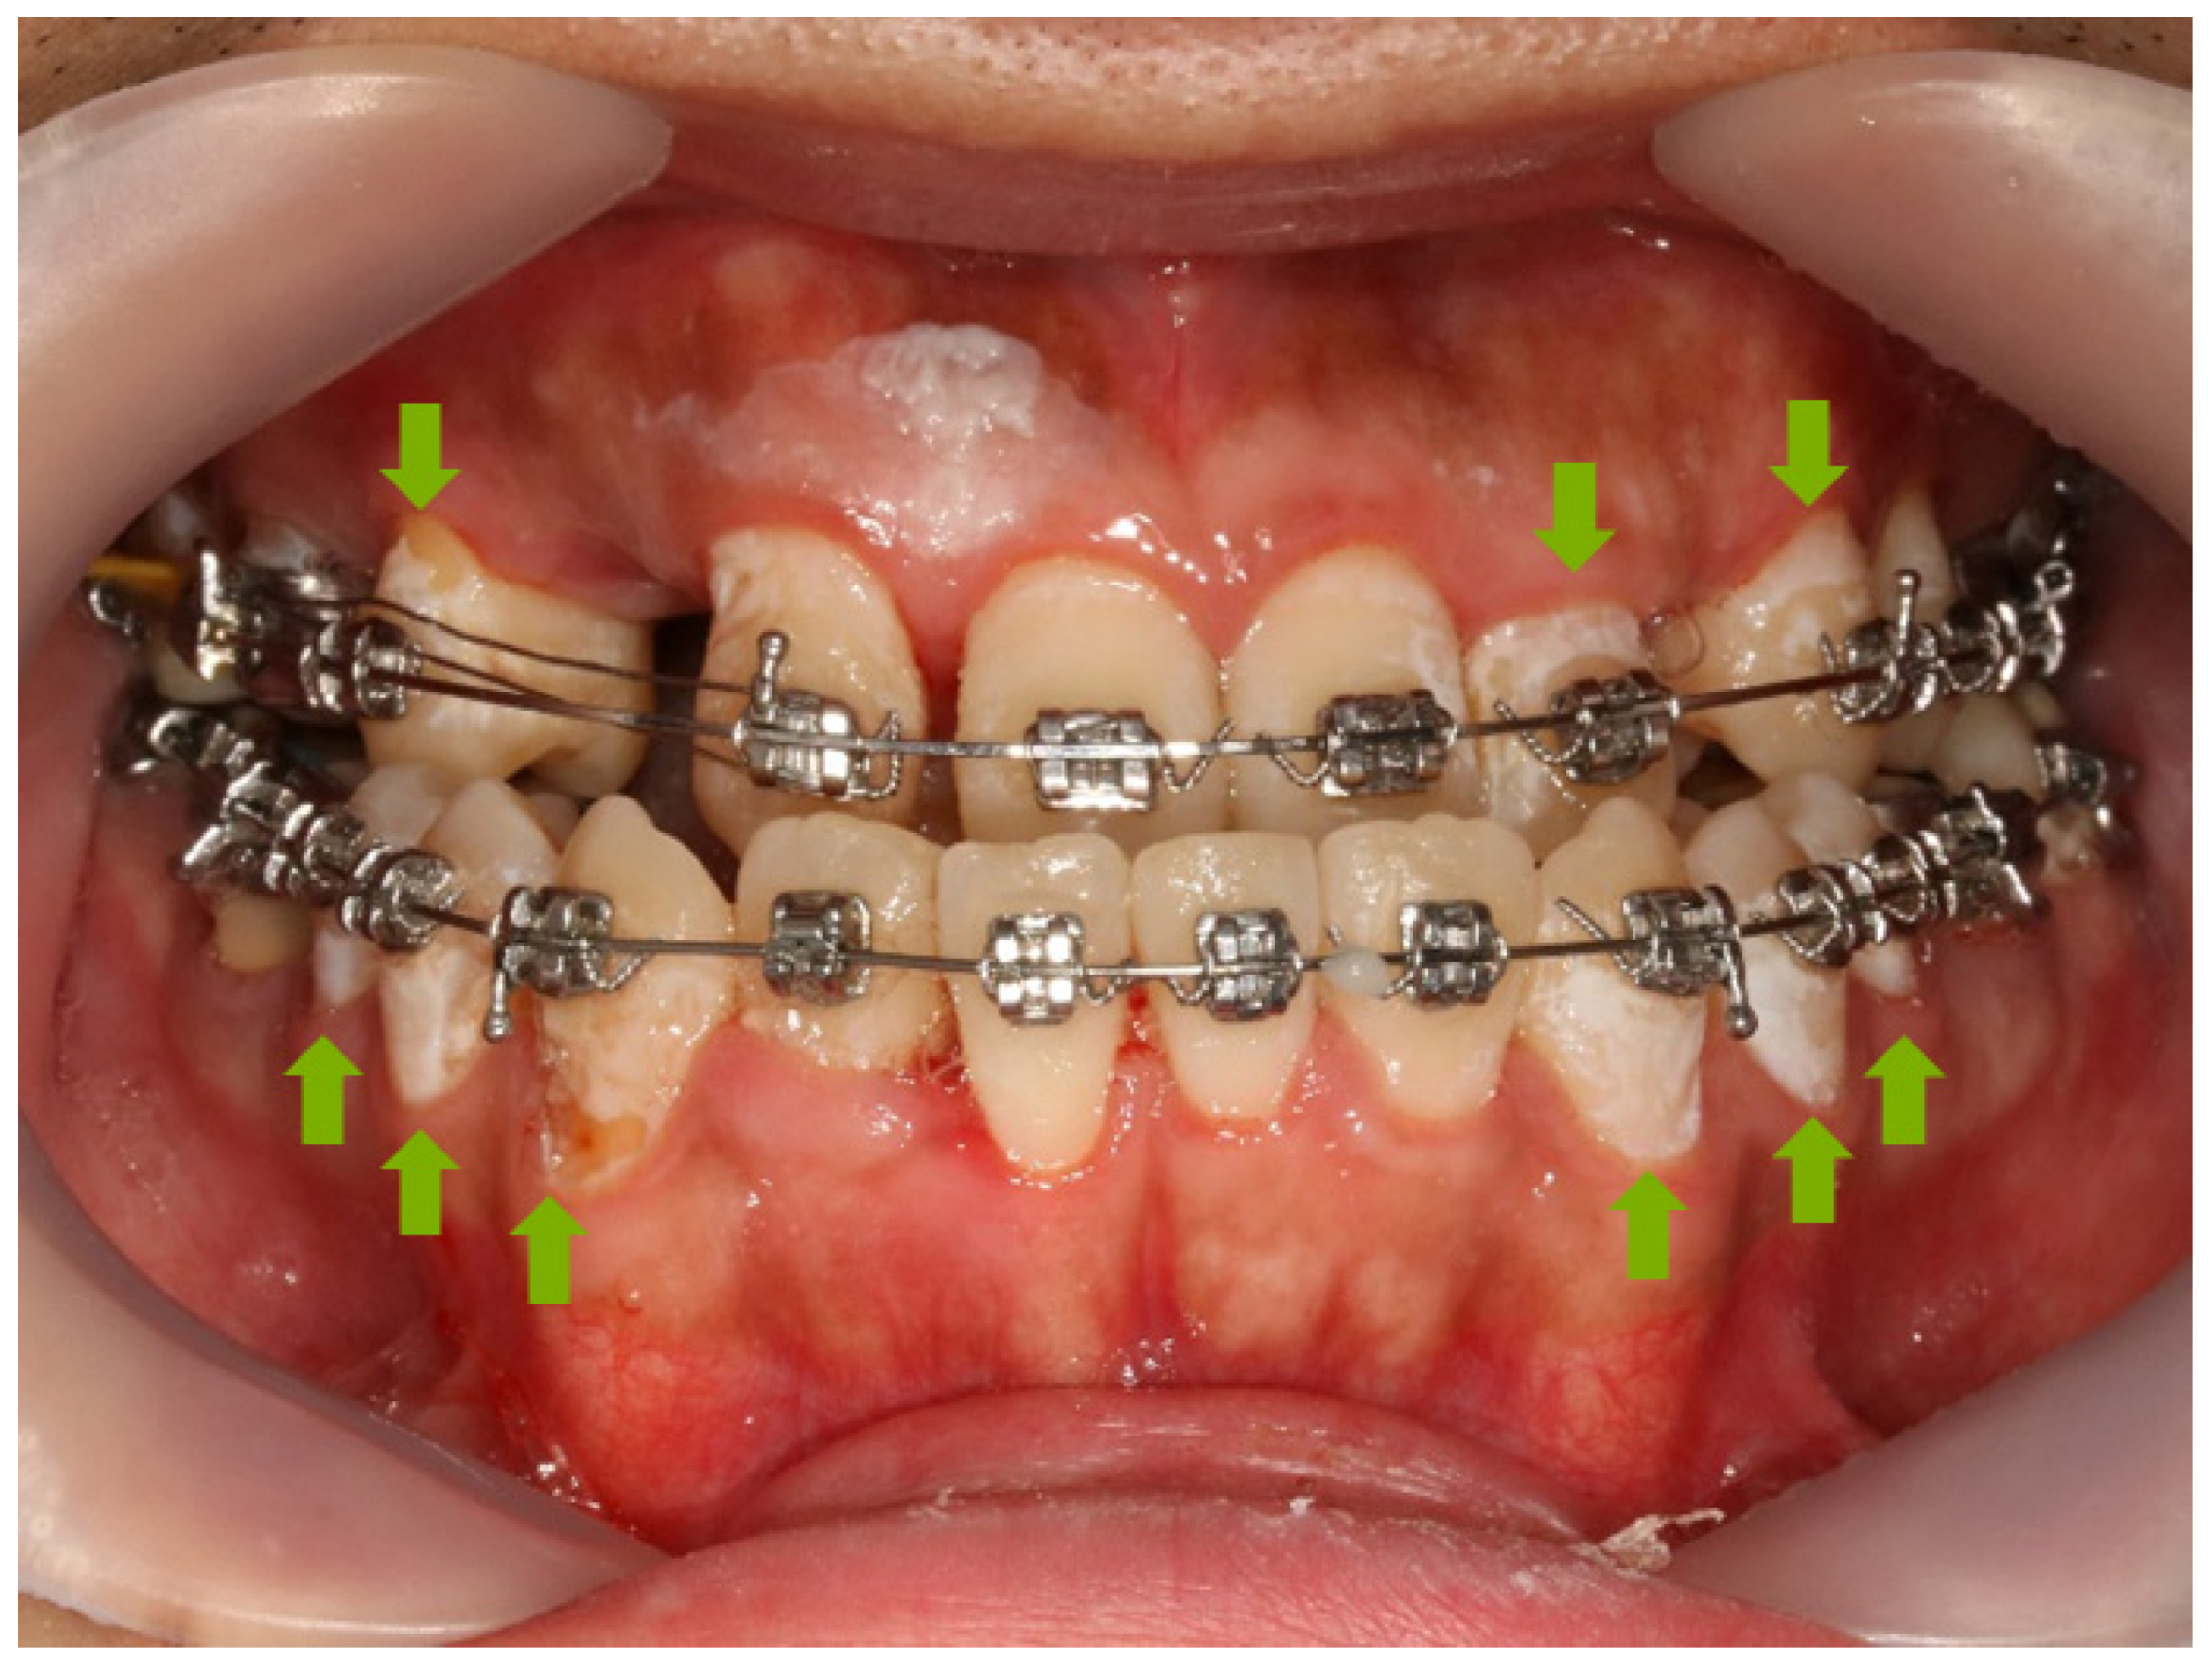

Figure 1.

The WSL on orthodontic patient. Green arrow indicates WSL on tooth.